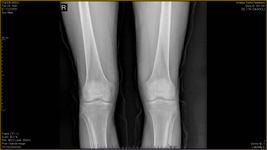

Öncelikle şunu söylemek istiyorum egzersiz kişiye özeldir ve ortopedik problemi olan kişilere mutlaka ayrıntılı bir muayeneden sonra verilmelidir. Problemin boyutu, evresi, anatomik yapınız, aktivite düzeyiniz; bunların hepsi egzersizleri değiştirebilir. Aynı problemi olan hastalara bile farklı egzersizler verilebilir bu sebeplerden dolayı. Benim size tavsiyem derdinizi dinlemeye ve ayrıntılı bir inceleme yapmaya zamanı olan kaliteli bir fizyoterapist bulun. Doktor tanısı ile beraber fzt ye gidin. Beklentilerinizi mutlaka iyi anlatın, eminim güzel sonuçlar alacaksınızdır. Bu biraz maliyetli olacaktır ama asla ameliyat olmak kadar değil.